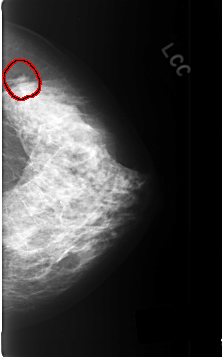

C_0358_1.LEFT_CC

LEFT_CC LINES 4640 PIXELS_PER_LINE 2880 BITS_PER_PIXEL 12 RESOLUTION 50 OVERLAY

FILE: C_0358_1.LEFT_CC.OVERLAY

TOTAL_ABNORMALITIES 1

ABNORMALITY 1

LESION_TYPE MASS SHAPE IRREGULAR MARGINS OBSCURED

ASSESSMENT 5

SUBTLETY 3

PATHOLOGY MALIGNANT

TOTAL_OUTLINES 1

BOUNDARY